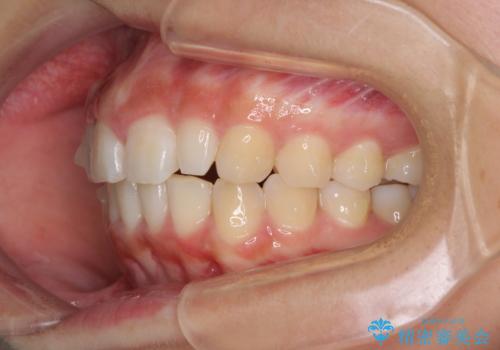

前歯のデコボコを治したい インビザラインによる矯正治療

- 前歯のデコボコ気になるとのことで来院された患者様です。

上下顎ともに歯列全体の後方移動とIPR(歯と歯の間を削る)によってデコボコが解消するように設計し、インビザラインにより治療を行うこととしました。

上顎左右前歯に矮小歯があるため、上顎の奥歯は下顎に対して相対的に前方に位置することになりました。

それでも奥歯の咬みにくさはなく、患者様には大変満足していただきました。